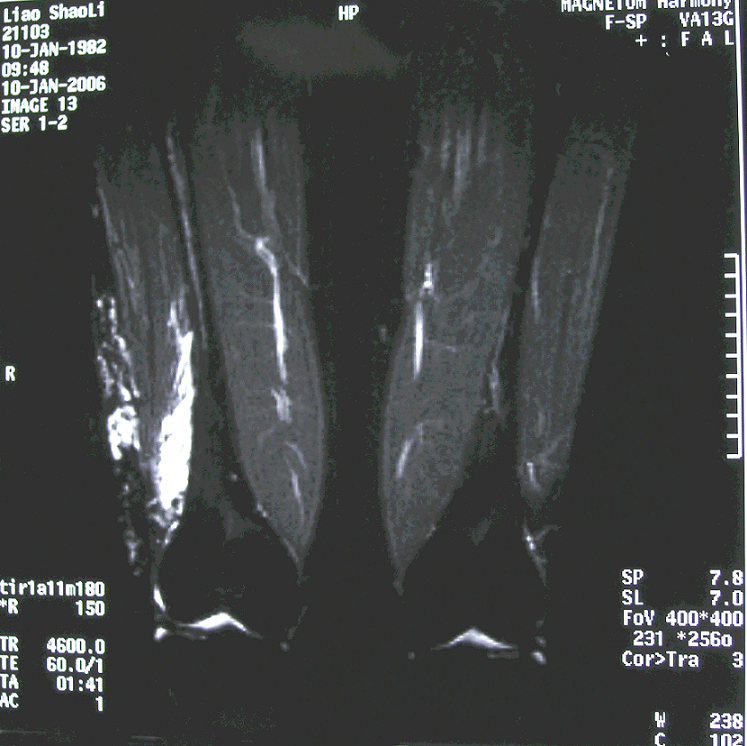

1.病例1:女 22岁,左小腿深部肌内血管瘤,入院后行后路肿瘤扩大切除术。

术前MRI

3.病例3:女 18岁,右下肢多发性深部肌内血管瘤,入院后行肿瘤扩大切除术。

右大腿MRI

右小腿MRI